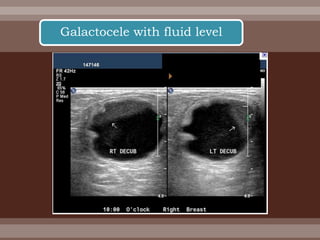

 Occasionally a milk duct becomes obstructed by

inspissated secretions, and milk may accumulate in

one or more mammary lobes.

 The amount is ordinarily limited, but an excess may

form a fluctuant mass—a galactocele—that may

cause pressure symptoms and have the appearance

of an abscess.

 It may resolve spontaneously or require aspiration.

Galactocele

Galactocele with fluid level